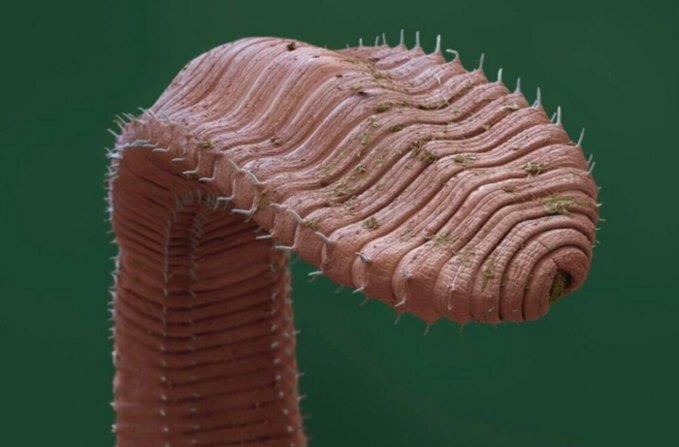

선명한 색감의 위성 사진처럼 보이는 대륙의 모습은 사실 우리 몸속 미세한 부분, 즉 혈관과 신경이 촘촘하게 얽혀 있는 갈색 지방 조직의 모습이다.

| ▲ 갈색 지방 조직의 형광 현미경 이미지. © Shamsi Lab, NYU College of Dentistry |